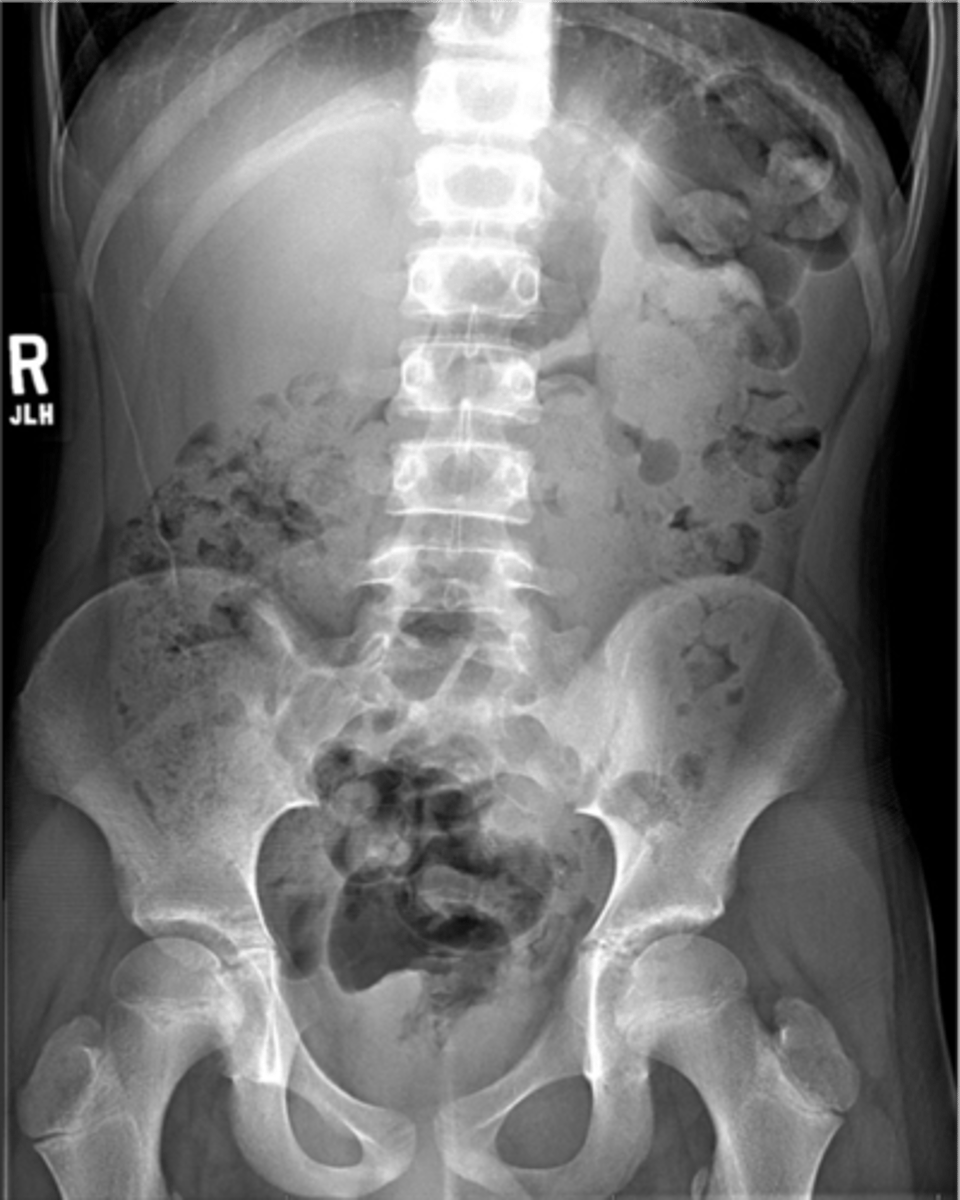

Abnormal organs on AXR

Hepatomegaly

Hepatomegaly (pic 2)